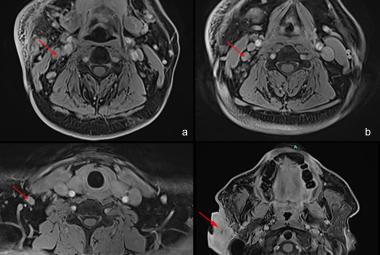

FIGURE 2: MRI images showed (a-c) enlarged and enhancing lymph nodes at levels 2, 3, and 4 of the right cervical neck regions; (d) lobulated soft tissue mass measuring 2.6 cm x 4.9 cm x 6.3 cm in the right pre- and postauricular space

Case Report

29 Jan, 2026

Recurrent Kimura Disease of the Submandibular Region After Prolonged Remission to Radiotherapy and Its Challenges